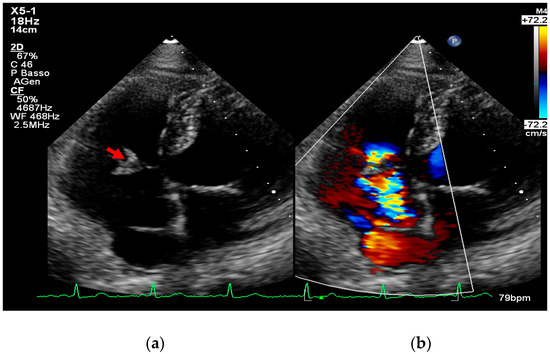

Multimodality Imaging in Infective Endocarditis: A Clinical Approach to Diagnosis

by Leonardo Brugiatelli, Francesca Patani, Carla Lofiego, Martina Benedetti, Irene Capodaglio, Pongetti Giulia, Francioni Matteo, Paolini Enrico, Nazziconi Marco, Kevin Maurizi, Furlani Giulia, Massari Arianna, Luciani Simone, Anselmi Benedetta, Gatti Chiara, Schicchi Nicolò, Fogante Marco, Tarsi Giovanni, Dello Russo Antonio, Di Eusanio Marco, Marini Marco and Fabio Vagnarelliadd Show full author list remove Hide full author list

Medicina 2025, 61(12), 2241; https://doi.org/10.3390/medicina61122241 - 18 Dec 2025

Infective endocarditis (IE) is a life-threatening condition with a rising incidence, demanding rapid and precise diagnosis. While echocardiography remains the cornerstone of initial evaluation, its limitations in complex cases—such as those involving prosthetic valves or cardiac devices—are well-known. This review synthesizes current evidence [...] Read more.

Infective endocarditis (IE) is a life-threatening condition with a rising incidence, demanding rapid and precise diagnosis. While echocardiography remains the cornerstone of initial evaluation, its limitations in complex cases—such as those involving prosthetic valves or cardiac devices—are well-known. This review synthesizes current evidence and guidelines to outline a practical, multimodality imaging approach for IE. We emphasize that integrating advanced techniques like cardiac computed tomography (CT) and [18F]-fluorodeoxyglucose positron emission tomography/computed tomography (FDG PET/CT) early in the diagnostic pathway, particularly in high-risk scenarios, significantly enhances diagnostic certainty, guides therapeutic decisions, and improves patient outcomes. A tailored imaging strategy, driven by clinical presentation and integrated within a multidisciplinary endocarditis team, is paramount for modern IE management. Full article

(This article belongs to the Special Issue Diagnosis and Treatment of Valvular Heart Diseases)

Show Figures

Figure 1